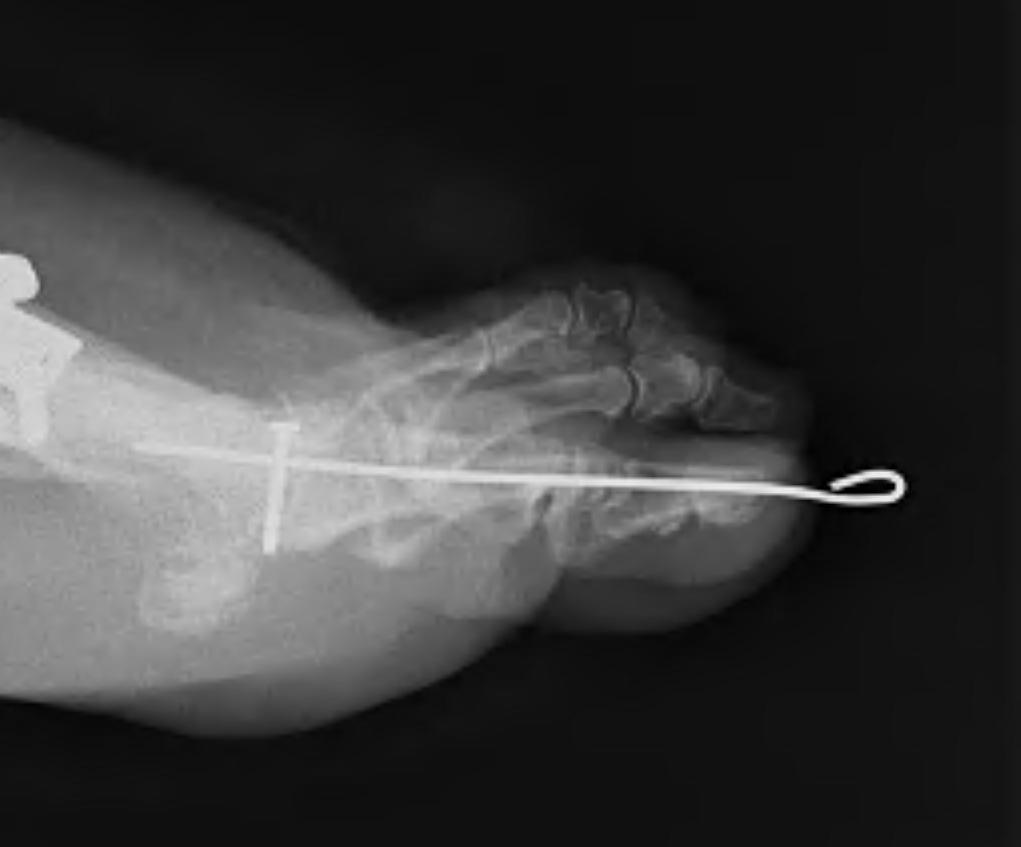

from www.boneschool.com

Hammer Toe The Bone School